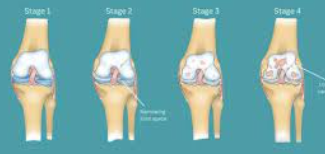

1단계: 경미한 연골 손상 증상

연골 손상 초기 단계에서는 증상이 미미하여 단순한 피로나 근육통으로 오인하기 쉽습니다. 주요 증상으로는 운동 후 가벼운 무릎 불편감, 아침 기상 시 약간의 강직감, 날씨 변화에 따른 무릎 불편감 등이 있습니다.

이 단계에서는 일상생활에 큰 지장이 없어 대부분 간과하게 되지만, 적절한 관리가 이루어지지 않으면 손상이 진행될 수 있습니다. 따라서 가벼운 증상이라도 지속되면 전문의 상담을 받는 것이 중요합니다.

2단계: 중등도 연골 손상 증상

연골 손상이 중등도로 진행되면 증상이 더욱 뚜렷해집니다. 계단 오르내리기, 쪼그려 앉기, 장시간 걷기 등의 활동에서 명확한 통증이 나타납니다. 무릎 관절에서 소리가 자주 나며, 무릎을 완전히 구부리거나 펴는 것이 어려워집니다.

이 단계에서는 무릎 부종이 눈에 띄게 나타나며, 활동 후 무릎이 무겁고 뻣뻣한 느낌이 지속됩니다. 진통제를 복용해야 할 정도의 통증이 발생하며, 수면 중에도 무릎 때문에 잠을 깨는 경우가 생깁니다.

3단계: 심각한 연골 손상 증상

연골 손상이 심각한 단계에 이르면 일상생활에 심각한 지장을 초래합니다. 평지 보행에서도 통증이 발생하며, 무릎을 움직일 때마다 심한 통증과 함께 관절음이 지속적으로 나타납니다.

무릎 관절의 변형이 육안으로도 확인되며, 무릎이 완전히 펴지지 않거나 구부러지지 않는 관절 강직이 나타납니다. 무릎에 힘이 빠지는 느낌과 함께 관절 불안정성이 심화되어 넘어질 위험이 증가합니다.